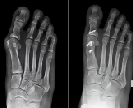

Figure 4 : radiographies avant et après chirurgie pour hallux valgus

Si la gêne devient importante, la chirurgie est indiquée. L’objectif est double :

-Corriger la déformation,

-Soulager les douleurs.

Figure 5 : Résultats avant et après chirurgie